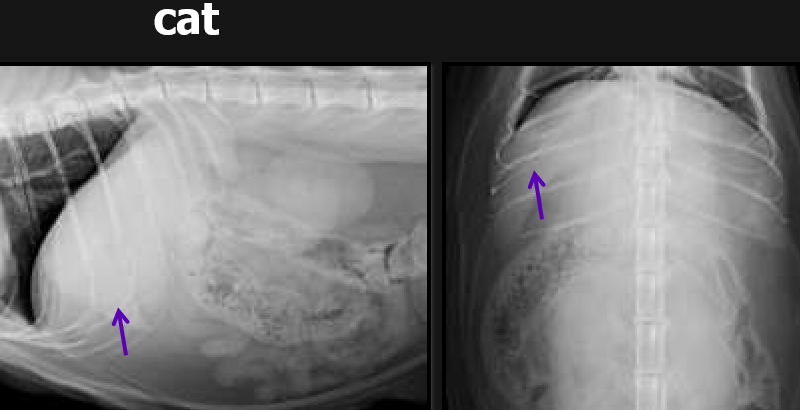

ventral and right

A fat cat’s small intestines are usually displaced _______.

Cat’s stomach’s are in the shape of a letter ____.